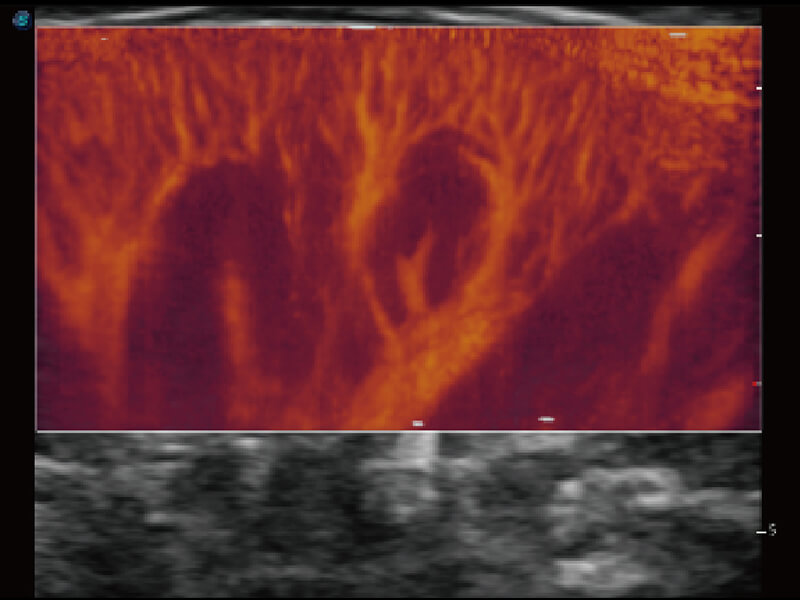

S60探头工艺,从前端信号处理每一个环节采集无损声学数据,真实还原组织原貌,再现解剖细节。